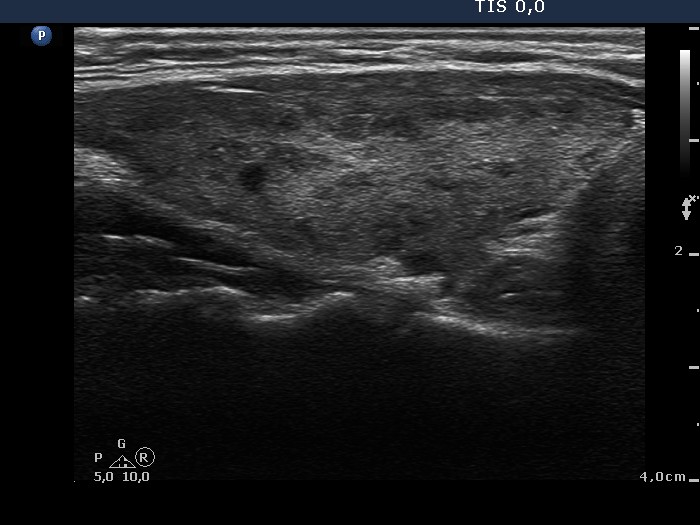

Case conp 038 (ultrasonographic picture 6)

Left lobe, longitudinal view.